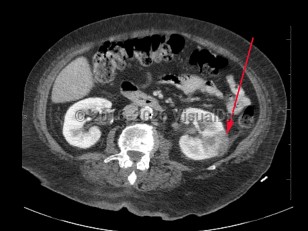

Psoas abscess

Polycystic kidney diseasePolycystic kidney disease